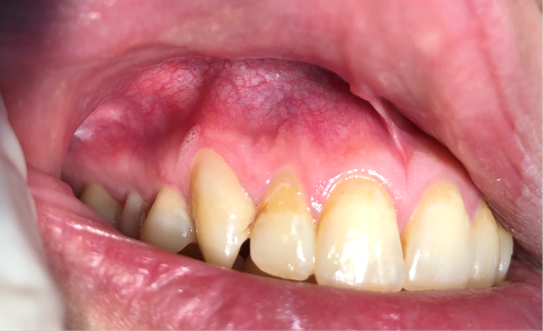

Patient Information: Male, 35 Years Old

8/27/2024,Chief Complaint: Weakness and discomfort in the right maxillary anterior teeth with mastication.